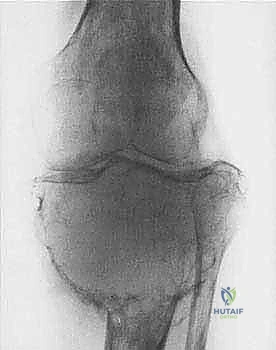

* الساركوما العظمية (Osteosarcoma): الأكثر شيوعاً، تظهر عادة حول الركبة (أسفل الفخذ أو أعلى القصبة).

تتميز هذه الأورام بقدرتها على اختراق الأنسجة المجاورة وتكوين ما يُعرف بـ "المنطقة التفاعلية" (Reactive Zone) أو الكبسولة الكاذبة، والتي تحتوي غالباً على خلايا سرطانية مجهرية. هذا المفهوم البيولوجي هو ما يوجه الدكتور محمد هطيف في تحديد مدى الاستئصال الجراحي.